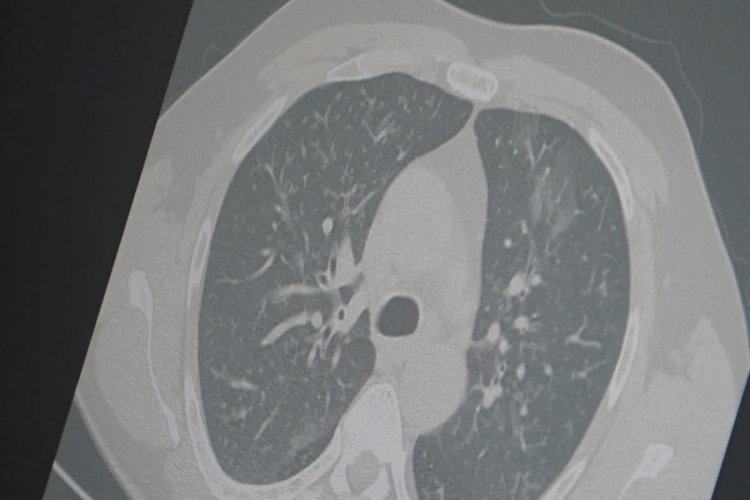

Son haftalarda ülke genelinde solunum yolu enfeksiyonlarında ciddi artış yaşandığın ifade eden Göğüs Hastalıkları Uzmanı Prof. Dr. Şevket Özkaya, aynı anda görülen influenza (grip), kovid-19 ve RSV virüslerinin toplumda "3'lü salgın" etkisi oluşturduğunu belirterek vatandaşları dikkatli olmaları konusunda uyardı.

Prof. Dr. Özkaya, son dönemdeki hava şartlarına dikkat çekerek, "Sonbahar ve yaz karışımı bir iklimin etkisiyle gün içinde ani sıcaklık değişimleri yaşanıyor. Aynı gün içerisinde dört mevsimi birden yaşıyoruz. Bu durum bağışıklık sistemini zayıflatıyor ve grip benzeri şikayetlerle başlayan hastalık tabloları, üç farklı virüsün etkisiyle uzamış bir hal alıyor" dedi.

Kovid-19'un "Frankenstein varyantı" olarak adlandırılan yeni türünün Türkiye'de de görüldüğünü ifade eden Prof. Dr. Özkaya, "Mevcut hastalarımız içinde kritik veya hayatı tehdit eden bir tablo yok. Ancak bu varyantın bulaşıcılığının yüksek olduğunu ve Avrupa ile Asya'da hızlı bir şekilde yayıldığını biliyoruz" diye konuştu.

Dr. Özkaya, grip ve kovid 19'un zatürreye dönüşme riski taşıdığını vurgulayarak, "Grip veya kovid sonrası birçok hastamızda hastalık akciğerlere iniyor ve zatürre olarak karşımıza çıkıyor. Hastaneye yatan hasta sayısında da artış gözlemliyoruz" şeklinde konuştu.

"En ufak grip benzeri şikayeti olan vatandaşlarımızın evlerinde dinlenmelerini öneriyoruz. Uzamış öksürük ve nefes darlığı yaşayanların ise mutlaka doktora başvurarak akciğer röntgeni çektirmeleri ve uygun tedaviyi almaları gerekiyor."